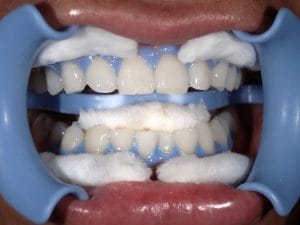

ホワイトニング

Case005 – ホワイトニングト

歯が欠けていて、隙間がある。

歯並びが気になる。

亀裂が入っている。

歯の無いところがある。

見える銀歯が気になる。

綺麗な口元になりたい。

という患者様の診療です。

上はジルコニアセラミックでかけているところを修復しながら、綺麗な歯並びで、患者様のお好きな白い歯に。

下の歯の無い所にはインプラント。

見える銀歯は外して綺麗な歯に修復。

また、ホワイトニングをして上の歯との色のギャップを少なくして、明るい口元にしました。